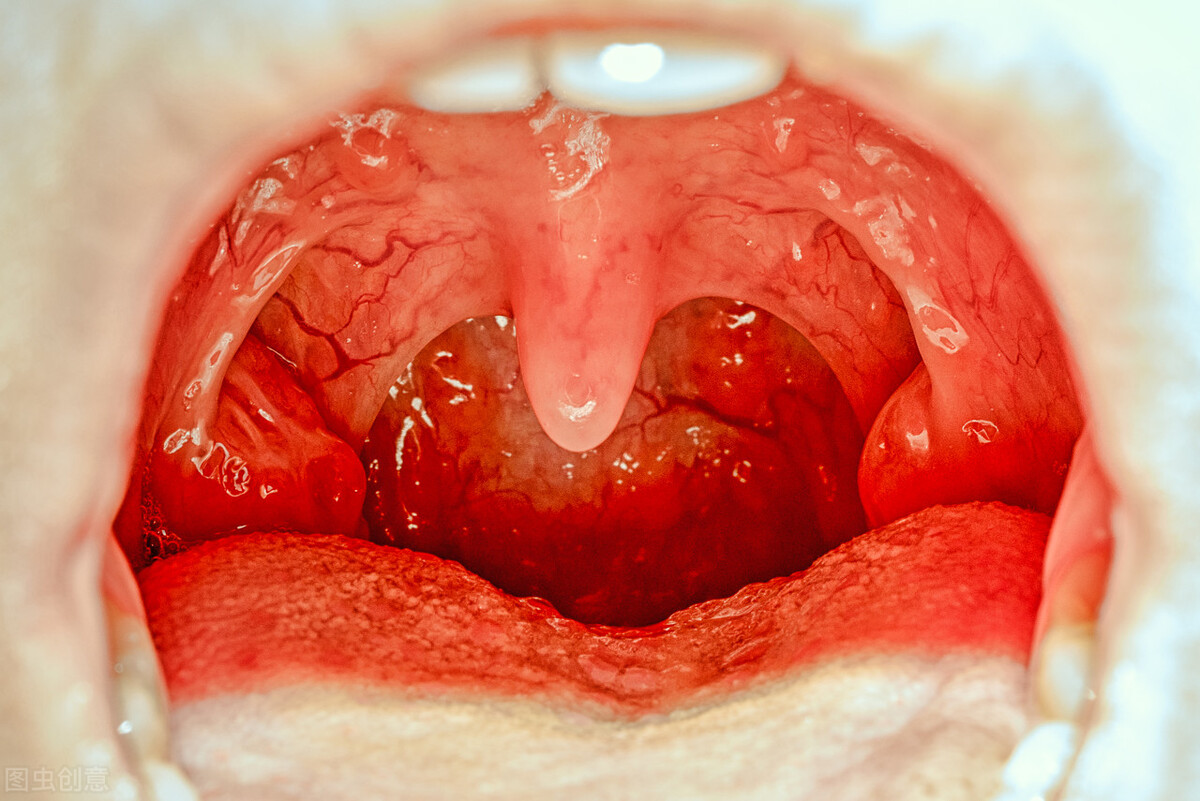

虽然我们常嘴上说,鱼刺卡喉咙,其实鱼刺卡的部位,最常见的还是在口咽部。这个位置是比较浅显的,包括扁桃体、扁桃体周围和舌根浅部,就是下图这些位置:

扁桃体